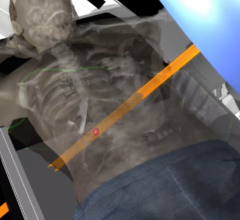

International medical imaging IT and cybersecurity company Sectra’s solution for medical education and clinical training, Sectra Education Portal, is now in use at the Amsterdam Center for Radiological Anatomy (ACRA). ACRA is part of the Academic Medical Center (AMC) in Amsterdam, the Netherlands.